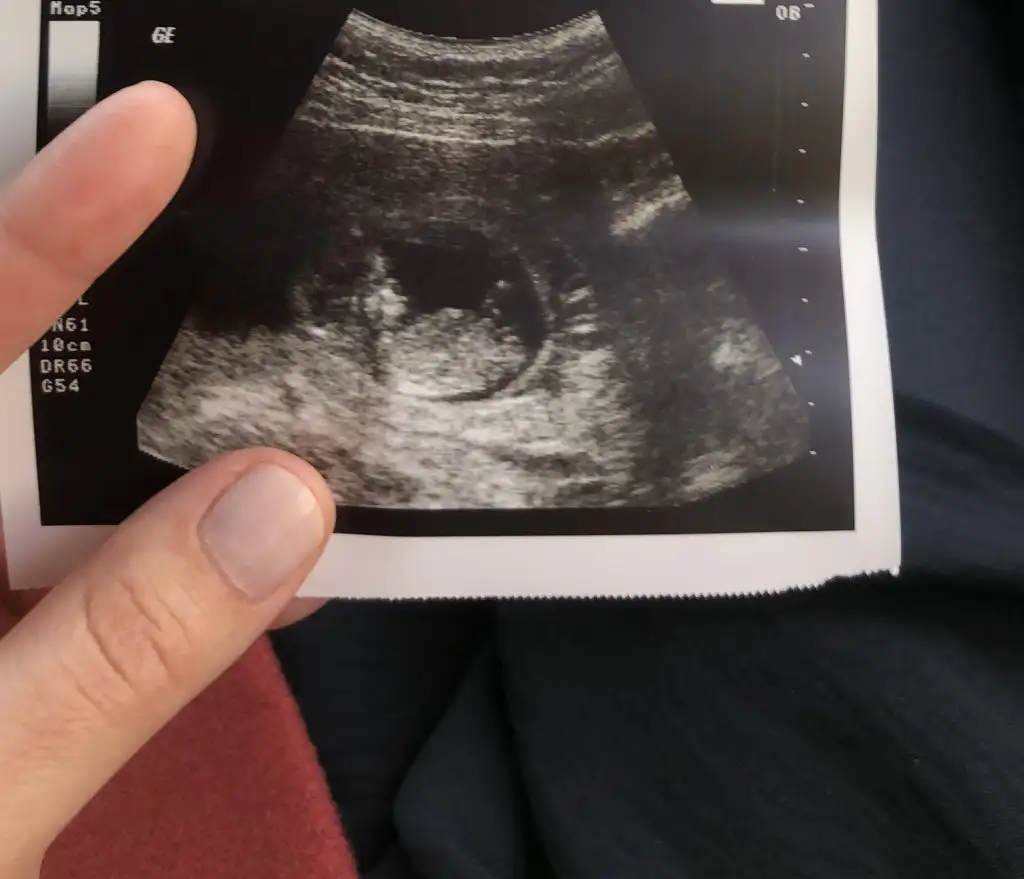

Kızlar yüklemeyi başarabildiysem bana da cinsiyet yorumu yapabilir misiniz :) ilk bebeğimiz 8+6 idi 9+1 gözüktü ultrasonda :)

Kızlar birde nub teorisi mi var:emir_bebek: Bilenler bize de bir tahmin de bulunabilir mi:) 11+3 idik bir hafta önden gidiyormuşEki Görüntüle 2789737

Canım nub pek belli olmuyor gördüğüm o ise kız gibi 30 derece altında :)) yaa inşallah 12.hafta bende böyle bir şey görürüm bin kere maşallah canım. 💙